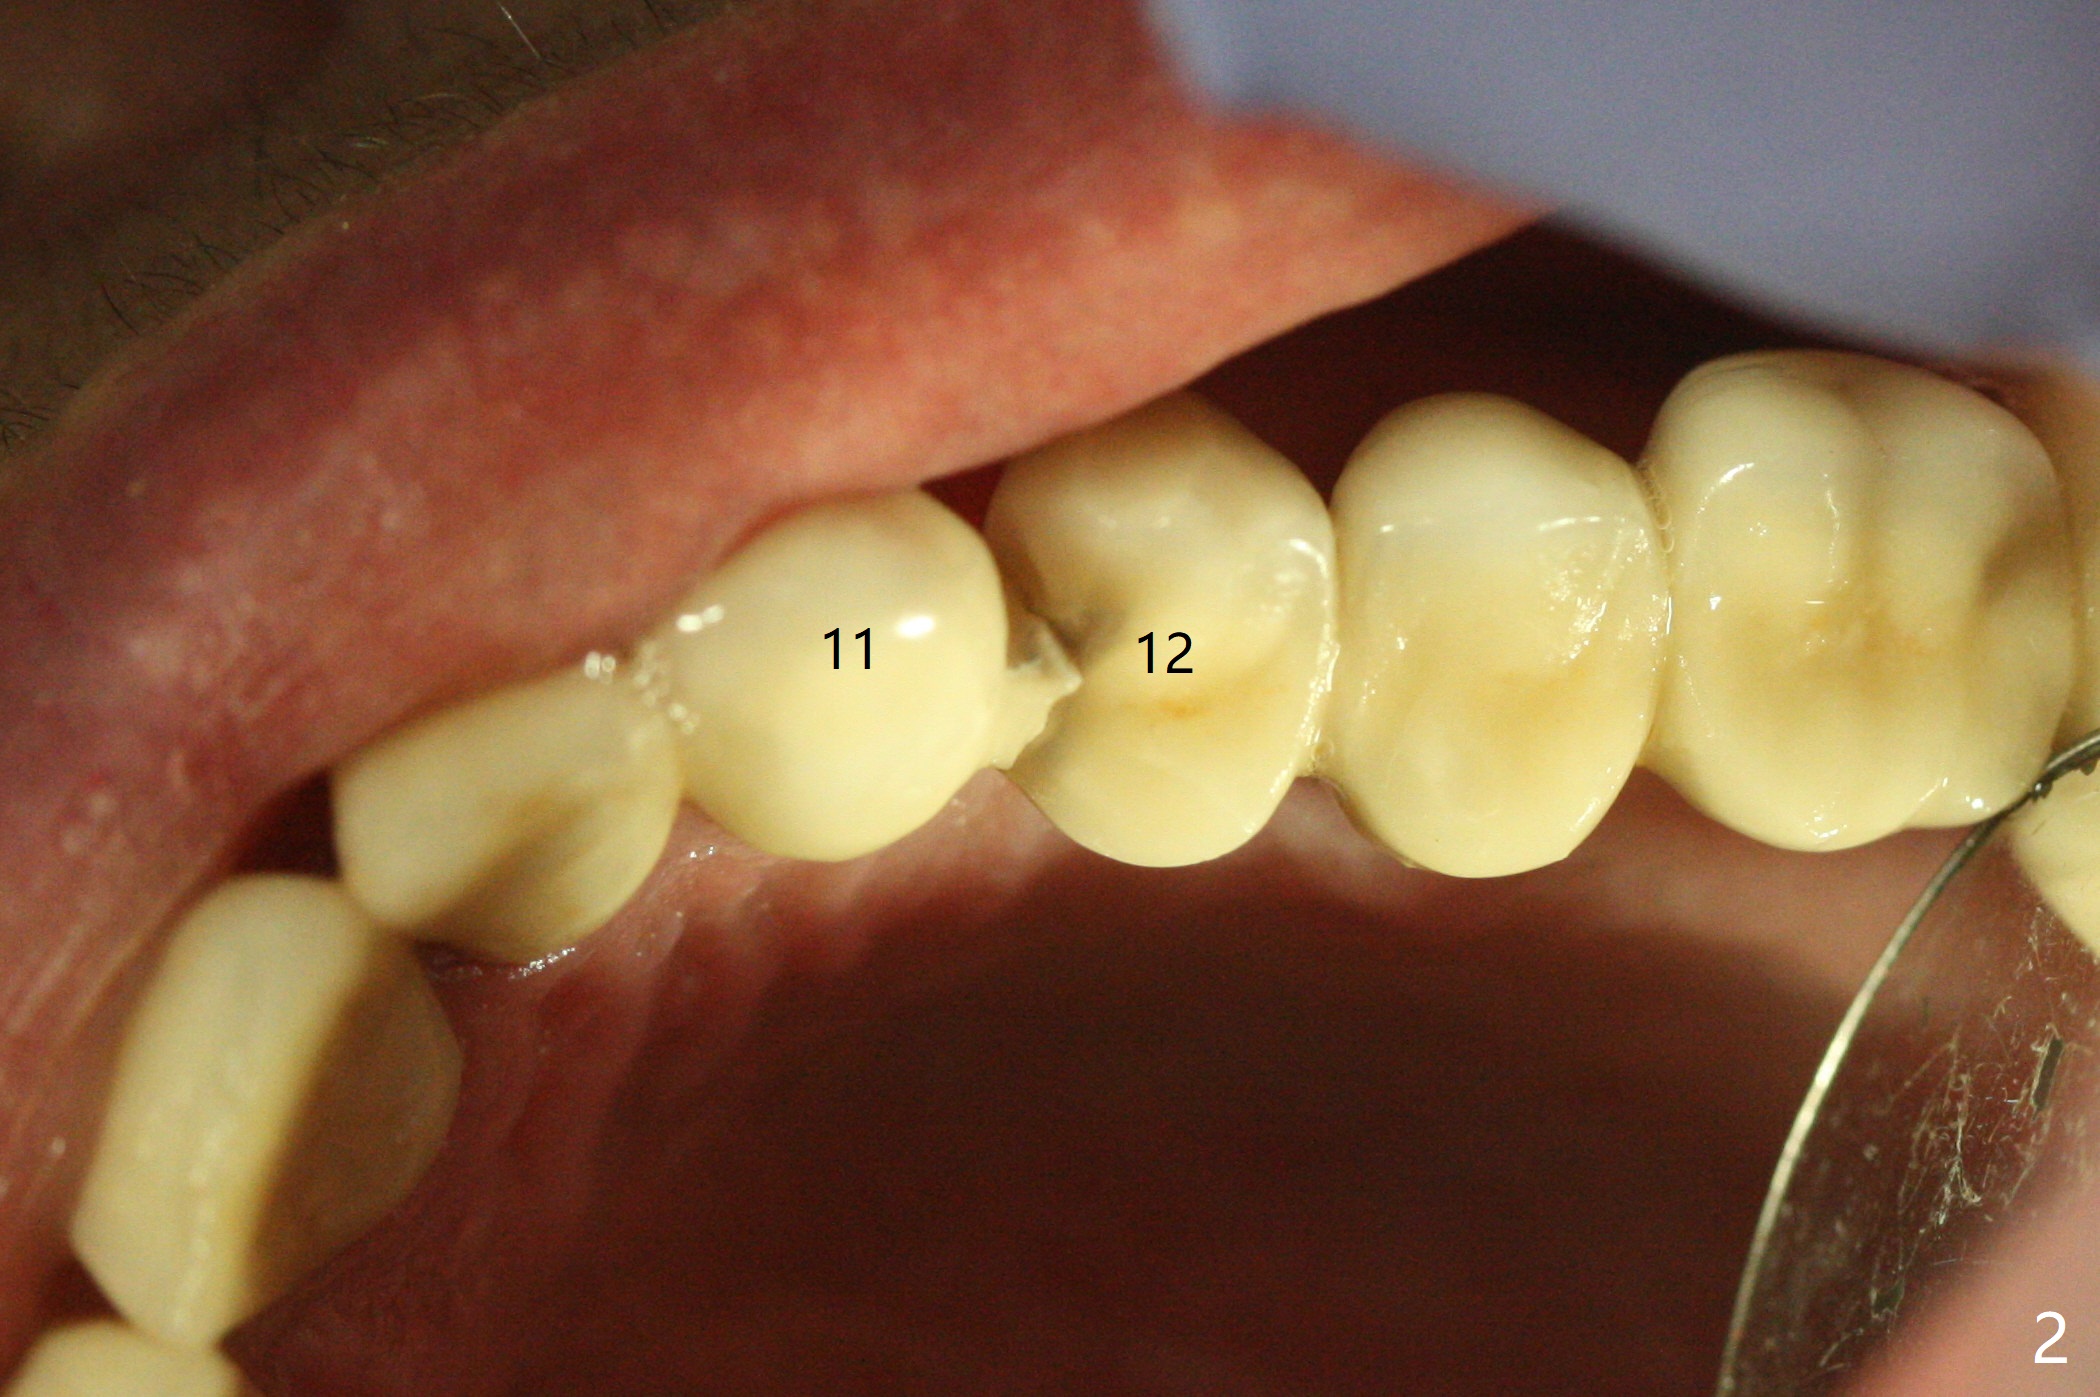

A 55-year-old woman is a bruxer (Fig.1). In 5 years the upper left FPD is fractured between #11 and 12 (Fig.2) and at #15 (Fig.3). Sectioning the FPD shows #15 non-salvageable (Fig.4). Implants will be placed at #12, 14 and 15. Sinus lift seems necessary at #14 (4 mm).